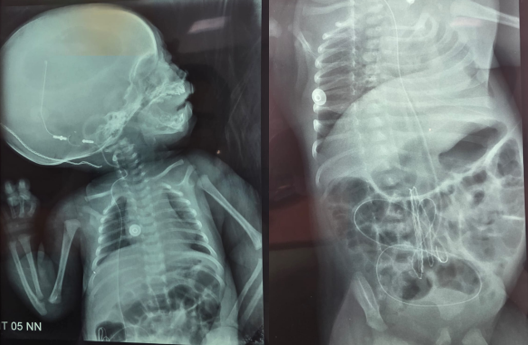

A CPS was inserted via a right parietal burr hole. The cyst fluid was clear and under pressure. The distal catheter was tunneled into the peritoneal cavity. Postoperative CT and radiographs (Figure 3) confirmed proper positioning. The infant’s symptoms resolved, feeding normalized, and developmental milestones were appropriate.

Figure 3: Standard radiographs, including frontal skull, chest, and abdominal views, confirming correct placement of the catheter.

At four months post-surgery, the parents noted extrusion of the catheter tip through the anus (Figure 4). The child was afebrile, alert, and had no abdominal tenderness. CT and radiographs (Figures 5 and 6) revealed sigmoid perforation with intraluminal catheter migration into the rectum. Importantly, no pneumoperitoneum, abscess, or signs of peritonitis were present.

Figure 6: AP radiographs of the thorax and abdomen showing anal extrusion of the distal cystoperitoneal catheter.